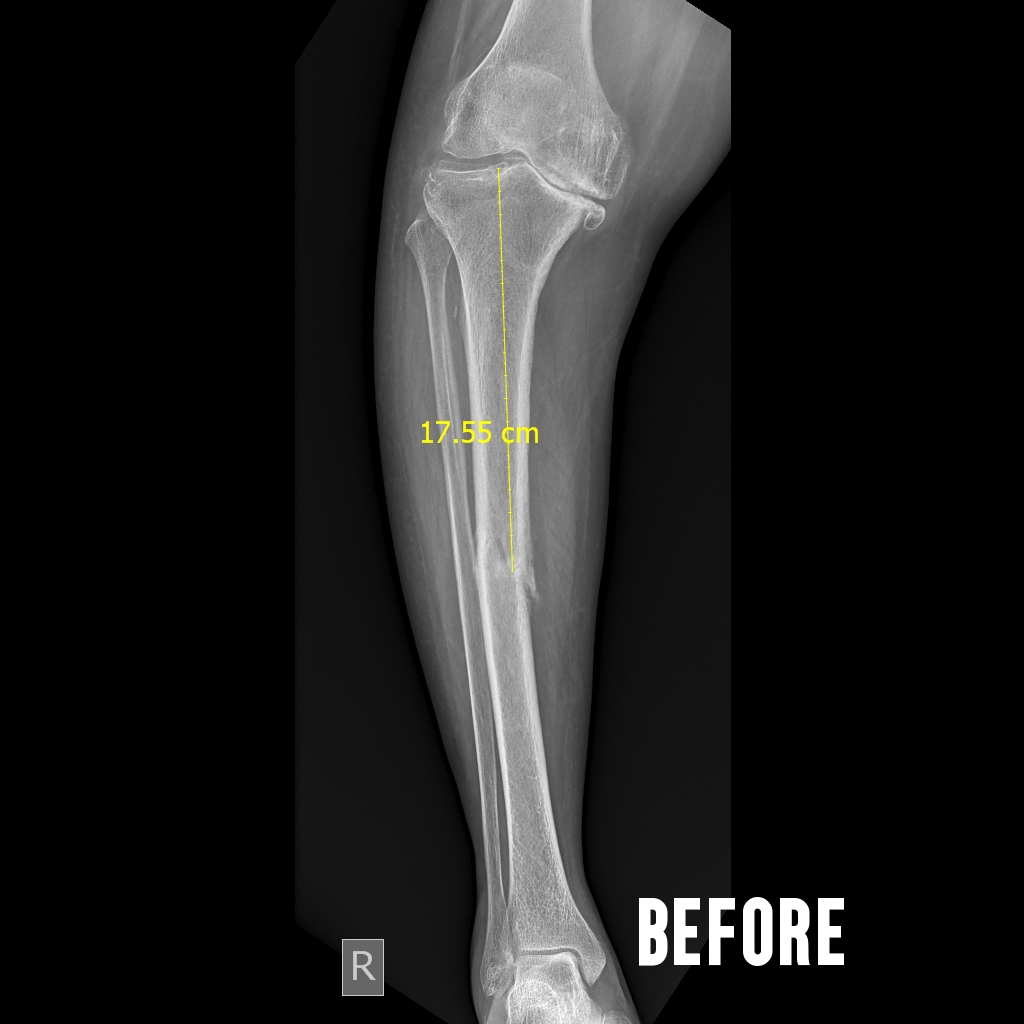

Senior surgeons with experience and expertise in the field perform knee replacement. Therefore, even complex deformed knee could be restored to normalcy. Pre-operative planning to post operative rehabilitation through surgical procedure is planned ahead so that nothing is left to chance. We are proud that our post operative infection rate is maintained at nil status for the past 5 years, thanks to the exceptional infection control measures. The type of implants is chosen after through discussion with the patient.